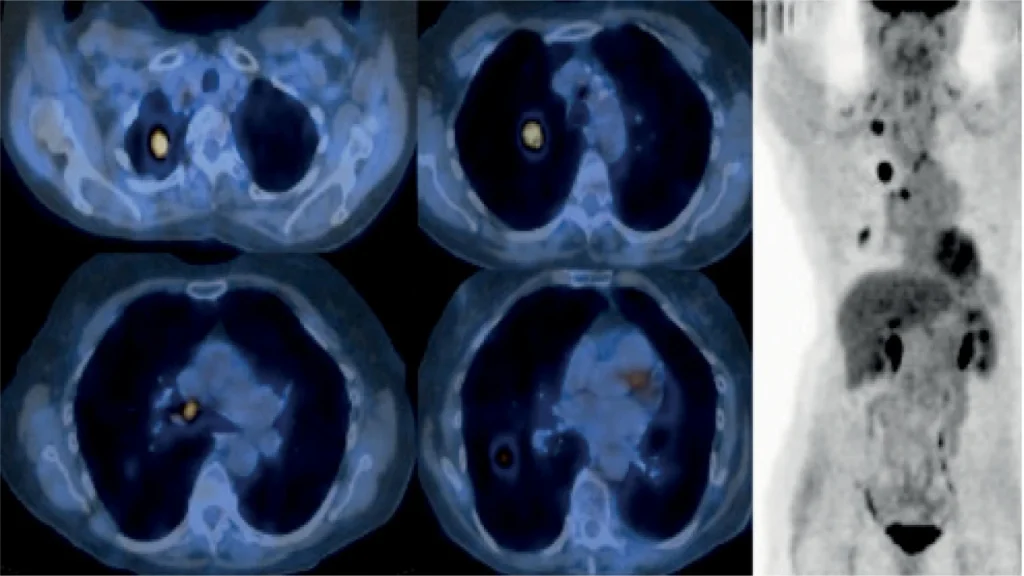

هزینه اسکن هسته ای سرطان چقدر است؟ اسکن هسته ای سرطان (Nuclear Scan) یک روش تصویربرداری پیشرفته پزشکی است که با استفاده از مواد رادیواکتیو و دستگاههای خاص، اطلاعات دقیقی از اندامها و بافتهای بدن ارائه میدهد. این مواد رادیواکتیو در بدن پخش میشوند و بسته به نوع سلولها یا فعالیتهای متابولیکی آنها، میزان جذب متفاوتی دارند. همین تفاوت جذب باعث میشود پزشک بتواند وضعیت اندامها، میزان فعالیت سلولی و حتی وجود سلولهای سرطانی را با دقت بالا مشاهده کند.

- در مقایسه با برخی روشهای دیگر مثل سیتیاسکن یا امآرآی، اسکن هستهای اطلاعات عملکردی سلولها را نشان میدهد، نه فقط شکل و اندازه اندامها.

Sometimes a special type of antibody made in the lab, called a monoclonal antibody, can be designed to stick to substances found only on the surface of cancer cells. A radioactive substance can be attached to the monoclonal antibody, which is then given into a vein. It travels in the bloodstream until it gets to the tumor and sticks to it. This causes the tumor to “light up” when seen through a special scanner. Your doctor can give you more information if it’s recommended that you have one of these tests.

گاهی اوقات میتوان نوع خاصی از آنتیبادی ساخته شده در آزمایشگاه، به نام آنتیبادی مونوکلونال، را طوری طراحی کرد که به موادی که فقط در سطح سلولهای سرطانی یافت میشوند، بچسبد. یک ماده رادیواکتیو میتواند به آنتیبادی مونوکلونال متصل شود و سپس به صورت وریدی تزریق شود. این ماده در جریان خون حرکت میکند تا به تومور برسد و به آن بچسبد. این باعث میشود که تومور هنگام مشاهده از طریق یک اسکنر ویژه “روشن” شود. در صورت توصیه پزشک برای انجام یکی از این آزمایشها، پزشک میتواند اطلاعات بیشتری در اختیار شما قرار دهد.دانشمندان همیشه در حال مطالعه ردیابهای جدید و تلاش برای بهبود ردیابهایی هستند که اکنون برای کمک به تشخیص و مرحلهبندی انواع خاصی از سرطانها استفاده میشوند.